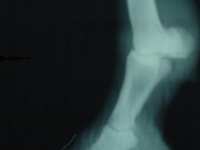

Bodi hatte starken Wendeschmerz und war auf die Zangenprobe sehr empfindlich. Der Tierarzt diagnostizierte klassische Hufrehe und Stefan war gefragt eine passende Lösung für Bodi zu finden.

Er wendete eine Kombination aus mehreren Arten des Rehebeschlages an um zu einem optimalen Ergebnis zu kommen.

Kombiniert wurden die Techniken des NBS (Natural Balance Shoeing) in Verbindung mit einem NBS Pad, angewendet mit einem normalen NBS Stahl Eisen.

Trachtenerhöhung wurde mittels Keilplatte und Einlegekeilen kurzfristig erzielt während die Trachtenebenen normal hergestellt wurden.

Die Zehe wurde am Schluss des Beschlages stark gekürzt um Bodi eine gute Möglichkeit zum Abrollen zu geben. Direkt nach dem Beschlag hatte sich das Gangbild wesentlich verbessert, so dass er in wenigen Wochen im Schritt fast keine Lahmheit mehr zeigte.